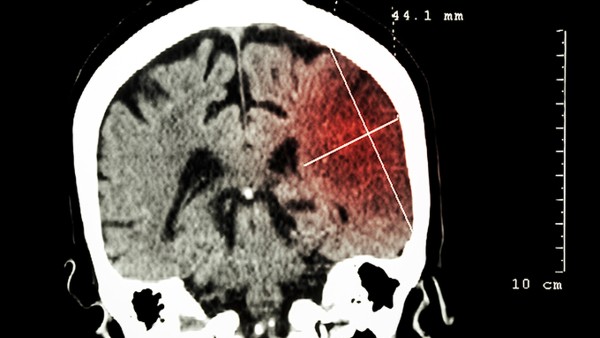

脑血栓形成是指血液流动缓慢、血液成分变化或血液粘度增加时形成血栓,导致血管堵塞,根据提供给大脑的动脉壁的病理变化。脑血栓形成部分脑梗塞,导致脑神经元功能障碍或癫痫发作异常放电。